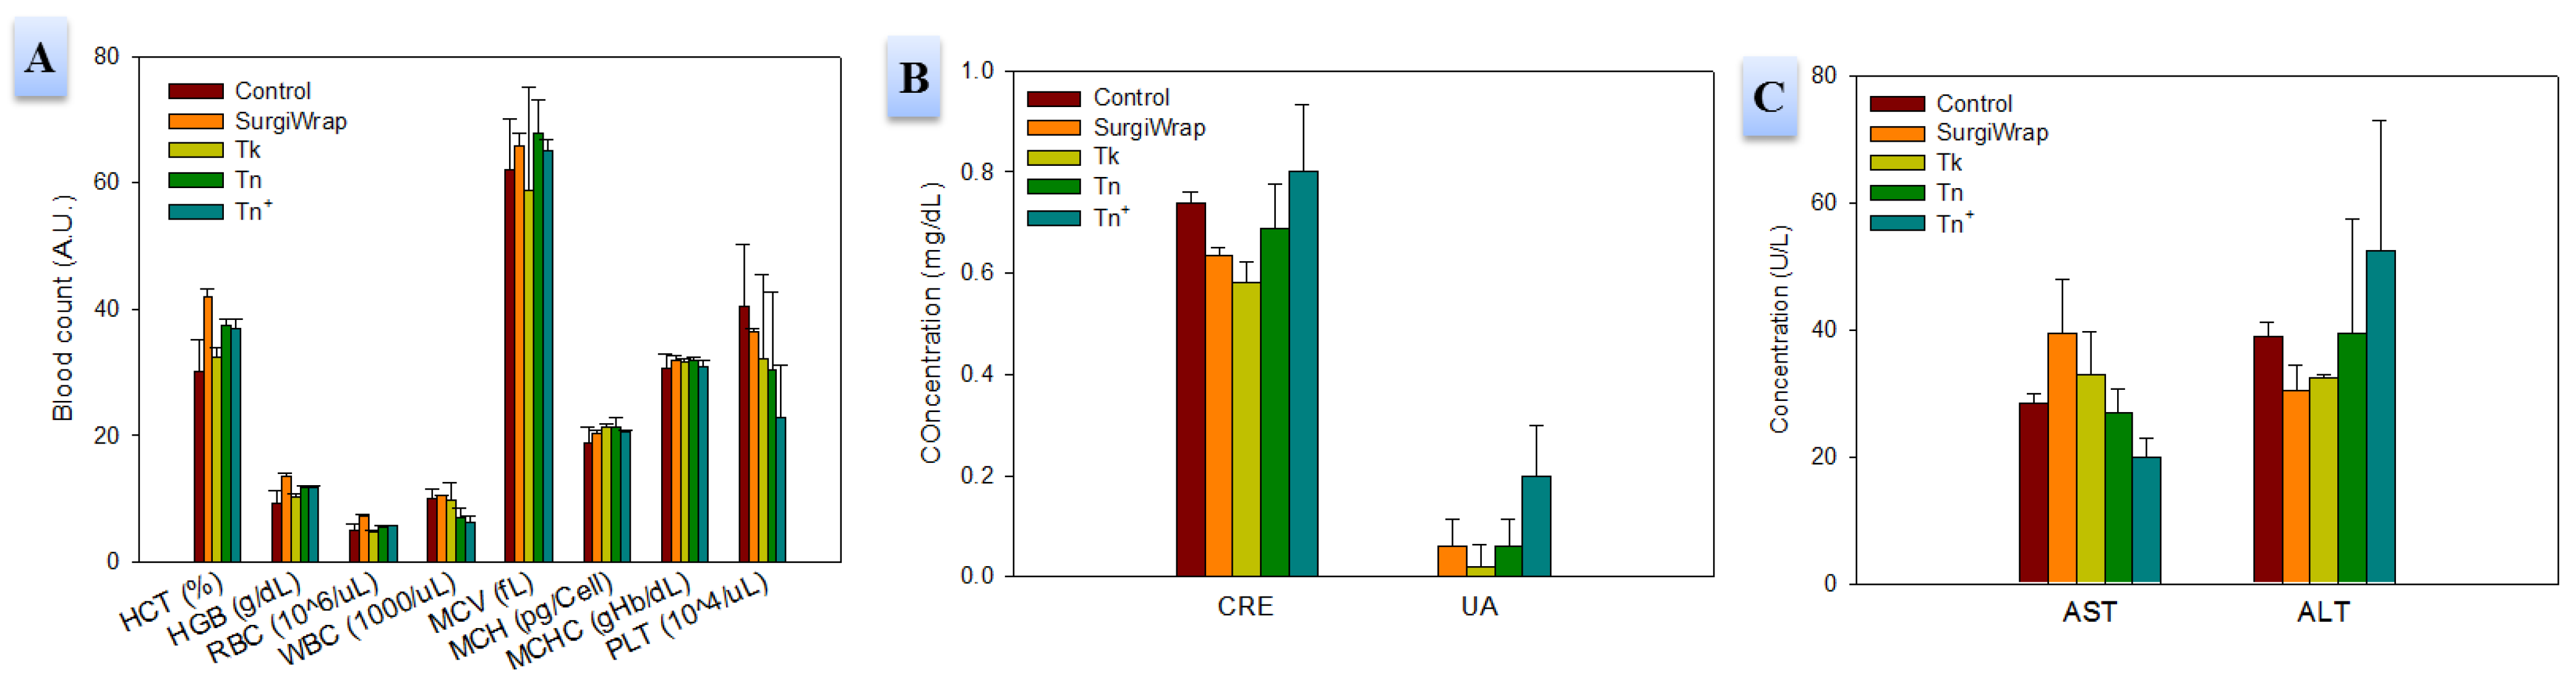

2.4. In Vivo Studies